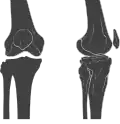

O joelho é uma articulação do corpo humano e de outros mamíferos. Formada pela extremidade distal do fêmur, pela extremidade proximal da tíbia (e pela patela (rótula).

O joelho é uma articulação sinovial complexa. Na verdade, ele possui duas articulações separadas:

O joelho permite os seguintes movimentos: flexão, extensão, assim como uma leve rotação lateral e medial. O joelho também possui mecanismos especiais de travamento e destravamento, relacionados ao movimento dos côndilos femorais no platô tibial.